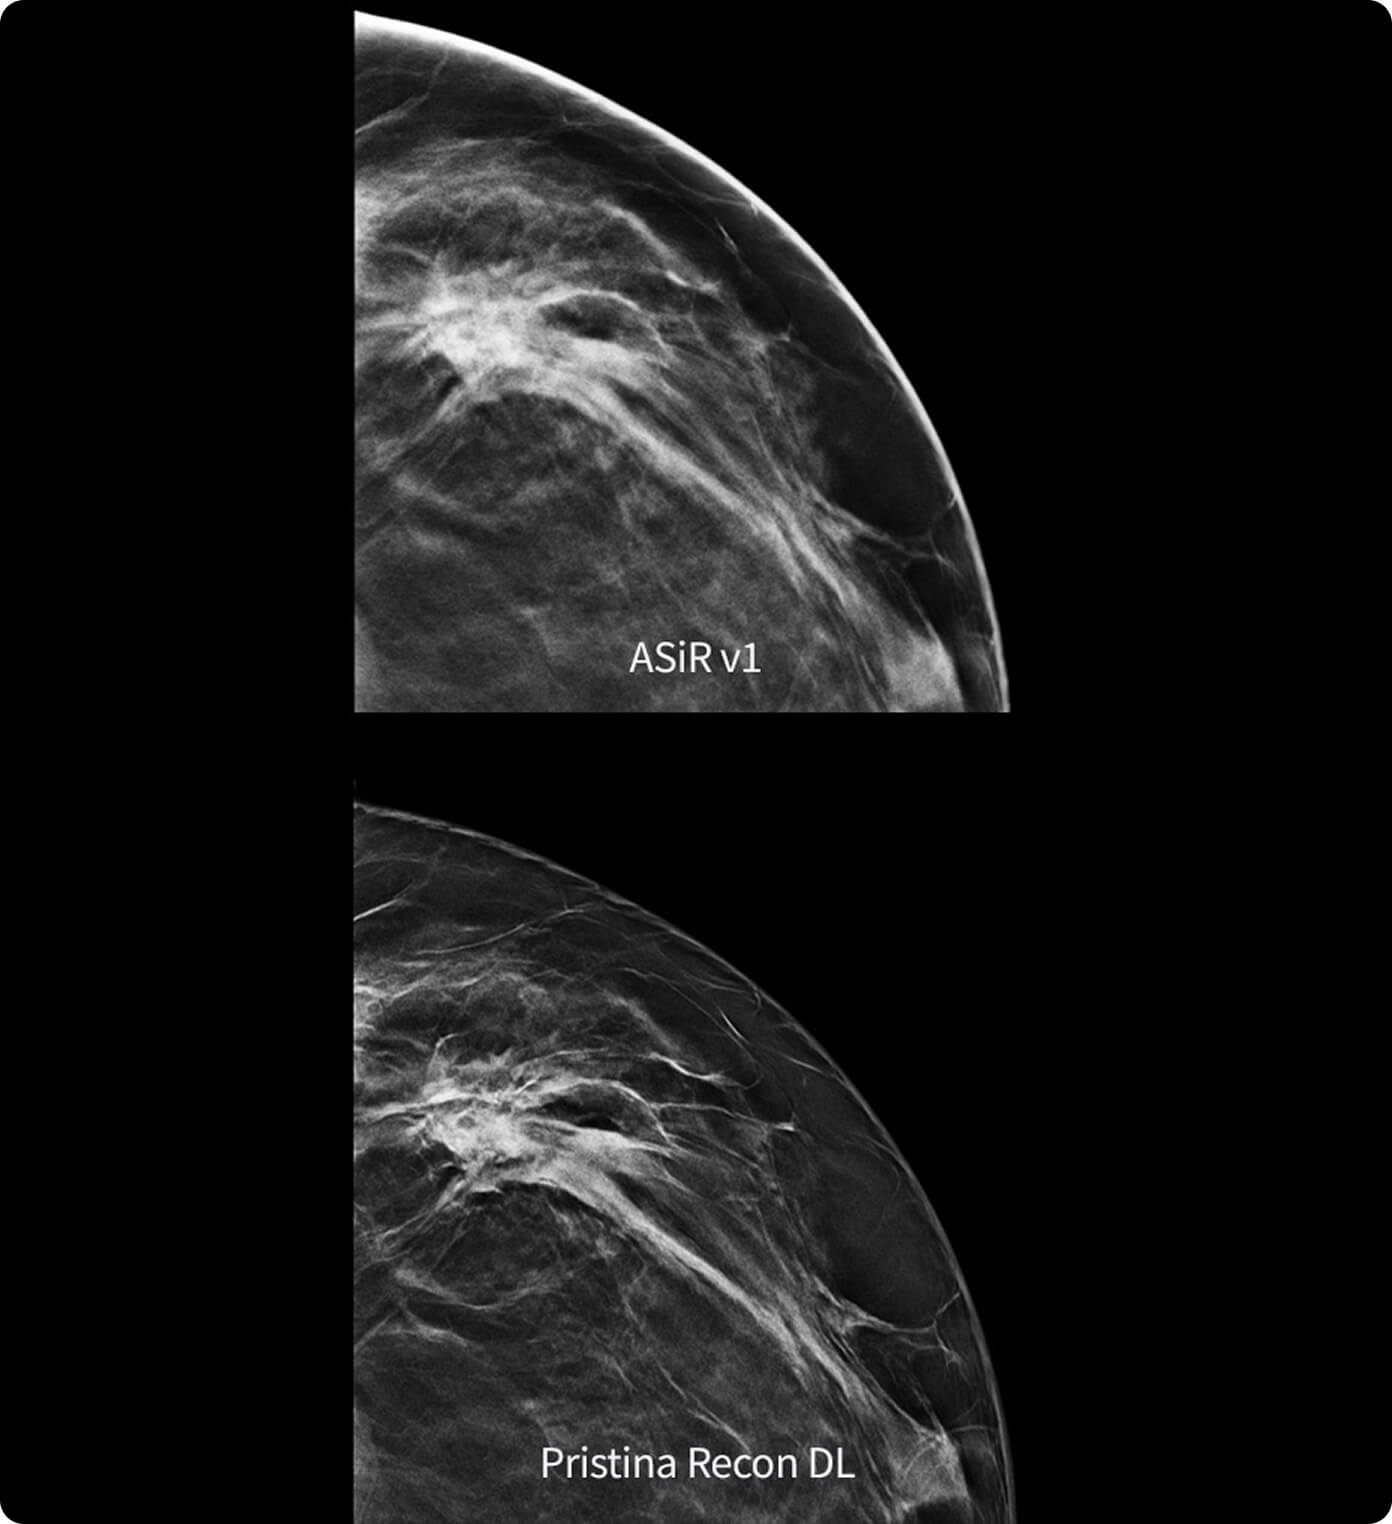

Kaliteden ödün vermeden kapsamlı ayrıntı, üstün kontrast, doku ve görüntü netliği sağlar.

%91

Tarama tekniğine ve rekonstrüksiyon parametrelerine bağlı olarak, aynı dozdaki FBP'ye kıyasla ASiR-V ile görüntü gürültüsünü azaltma.4

3. 3. Klinik uygulamada ASiR-V kullanımı klinik işlem, hasta boyutu, anatomik konum ve klinik uygulamaya bağlı olarak BT hasta dozunu düşürebilir. Uygulanacak klinik işlemde tanısal görüntü kalitesi elde etmek için uygun dozu belirlemek üzere bir radyolog ve hekimle konsültasyon yapılmalıdır. ASiR-V ve FBP karşılaştırması için referans fabrika protokolleri kullanılarak Düşük Kontrastta Saptanabilirlik (LCD), Görüntü Gürültüsü, Uzaysal Çözünürlük ve Artefaktlar değerlendirilmiştir. Model gözlemci yöntemi kullanılarak 0,625 mm kesitlerde LCD ölçülmüş ve hem kafa hem de vücut modları için MITA CT IQ Fantom kullanılarak (CCT183, Fantom Laboratuvarı) test edilmiştir.